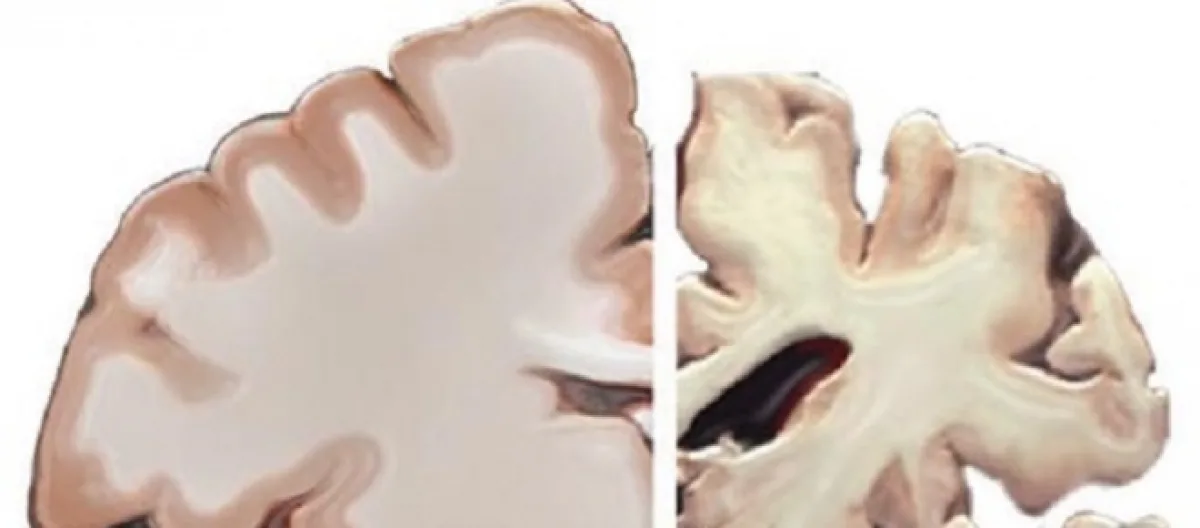

The physical manifestations of Alzheimer’s consists of neural tangles and plaques that interfere with the brain’s ability to function. The decline is slow but inexorable. First memory starts to go, then intelligence, and then the sufferer is an empty shell, robbed of self-identity, entirely dependent on others for daily existence.